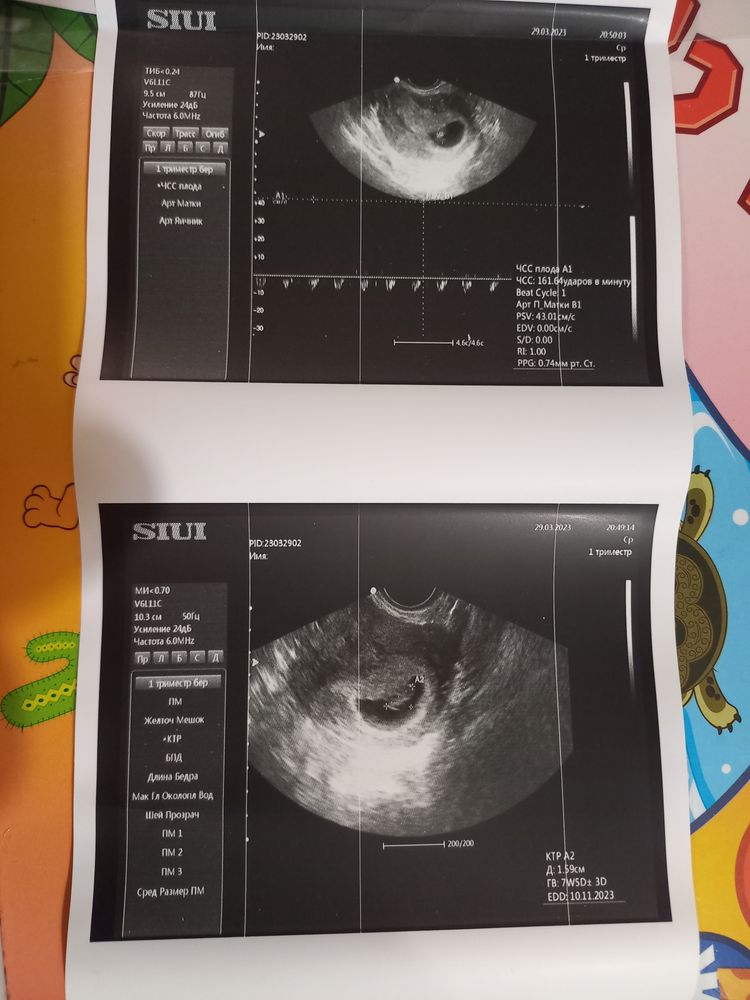

,думала,что все нормально будет и все тонусы уйдут,но сегодня и по передней и по задней стенке тонус.Бедный малышуля как будто зажат там.Сердечко бьется-ЧСС-161/мин.Но переживаю сильно по поводу этого расширения.Доктор говорит-впринципе ничего критичного,контроль узи-скриннинг в 12 недель.А в выписке написала:"УЗ-угроза невынашивания".Девочки,все ведь не так критично?

Сегодня ровно 8 недель,сходила на узи в хеликс.Неделю назад по узи был тонус

Выписала мне еще интравагинально Праджисан по 100×2 раза в день,это плюсом к Дюфастону(3 раза с сутки),магний Б6.Полный покой:половой,моральный,физический.К гинекологу своей 3 апреля,вставать на учет.